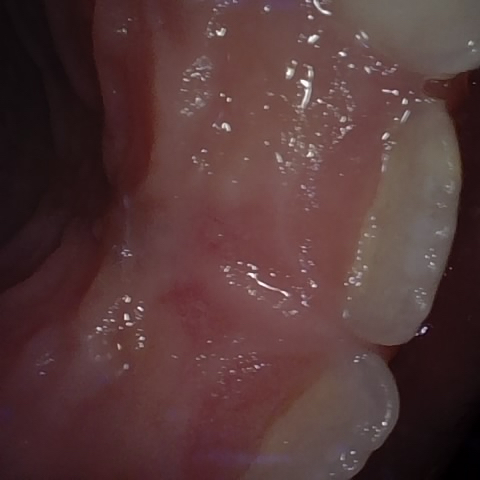

Annotated as "Good"